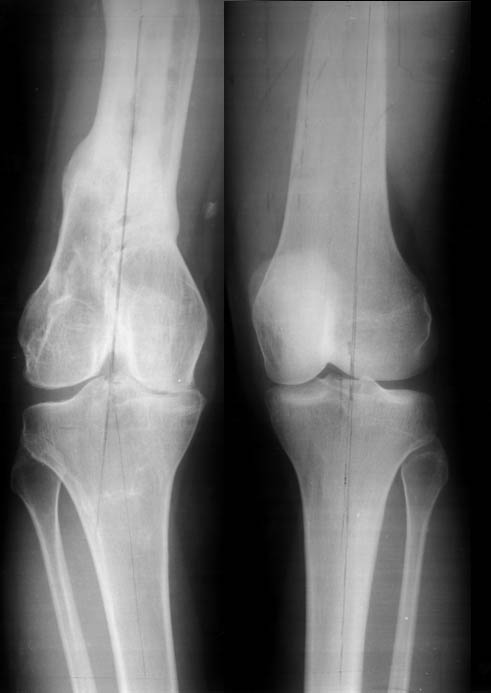

Переломы конечностей лечились АВФ.В настоящее время стойкая разгибательная контрактура правого коленного сустава (сгибание 105-110 гр., разгибание 160-165 гр.), варусная деформация, болевой синдром.

Вопросы: 1.Определение уровня корригирующей остеотомии для устранения варусной деформации правой нижней конечности (остеотомия на бедре или голени)?

Даже по этим коротким снимкам видно, что варусная деформация на уровне бедра. Хотя для полноценной оценки оси сделать надо снимок всей конечности, от таза до стопы. Наклеить метки на кожу, по которым сделать склейку. И профиль бы тоже неплохо посмотреть.

Уважаемый Антон, видимо перелом большеберцовой кости на механическую ось не повлиял, но явно варусная деформация усугубляется повреждением наружного связочного аппарата (МКС.... Просится поднагрузочный R-снимок конечности и корригировать, на мой взгляд, надо бедро (+ остеотомия, если планируется мобилизация коленного сустава).